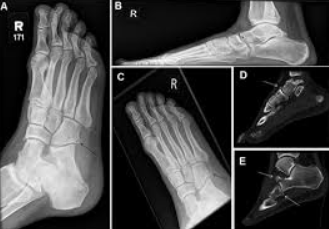

A physical examination is usually done, but it may be difficult to carry out due to pain. Diagnostic measures may include: blood and urine tests; neurological and muscle strength examinations; magnetic resonance imaging (MRI); and computed tomography (CT) scan. Muscle strength is tested and graded on a scale of 0 (none) to 5 (normal). A muscle enzyme test, creatine kinase (CK-MM), muscle biopsy, and electromyogram (EMG) may be done.

1. X-ray evidence of minute multiple scattered foreign bodies indicating intermuscular trauma and explosive effect of the missile.